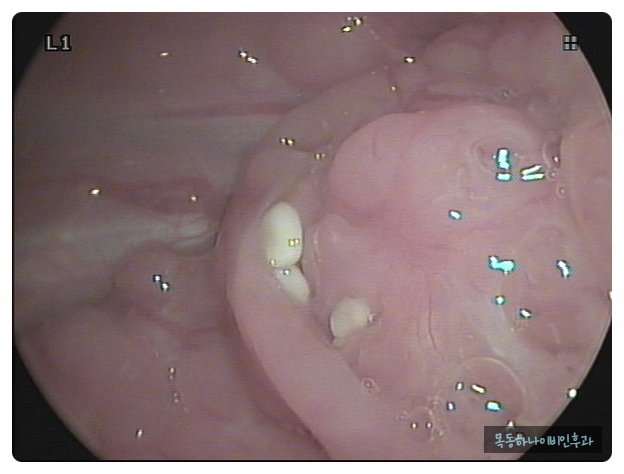

편도결석은 편도선 안에 있는 얇고 깊은 홈에 음식물 찌꺼기나 각종 분비물이 침착하여 돌처럼 단단해진 물질입니다. 크기는 눈곱처럼 작기도 하지만 손톱 크기 정도의 큰 결석이 나오기도 합니다. 색깔도 다양하고 흰색에서 노란색이나 치즈색을 보이기도 합니다. 건강한 성인에서도 약 10%에서 편도결석이 관찰됩니다. 물론 편도 결석이 있습니다만, 결석이 있다는 것을 알지 못하는 분도 많습니다.

편도결석은 눈으로 확인하시면 바로 진단이 가능합니다. 양치질과 기침을 하다가 튀어 나오거나 눈에 보이는 경우도 종종 있습니다. 증상은 있지만, 눈으로 관찰할 수 없을 때 병원에서 후두 내시경으로 목구멍 안쪽에서 관찰될 수도 있습니다.